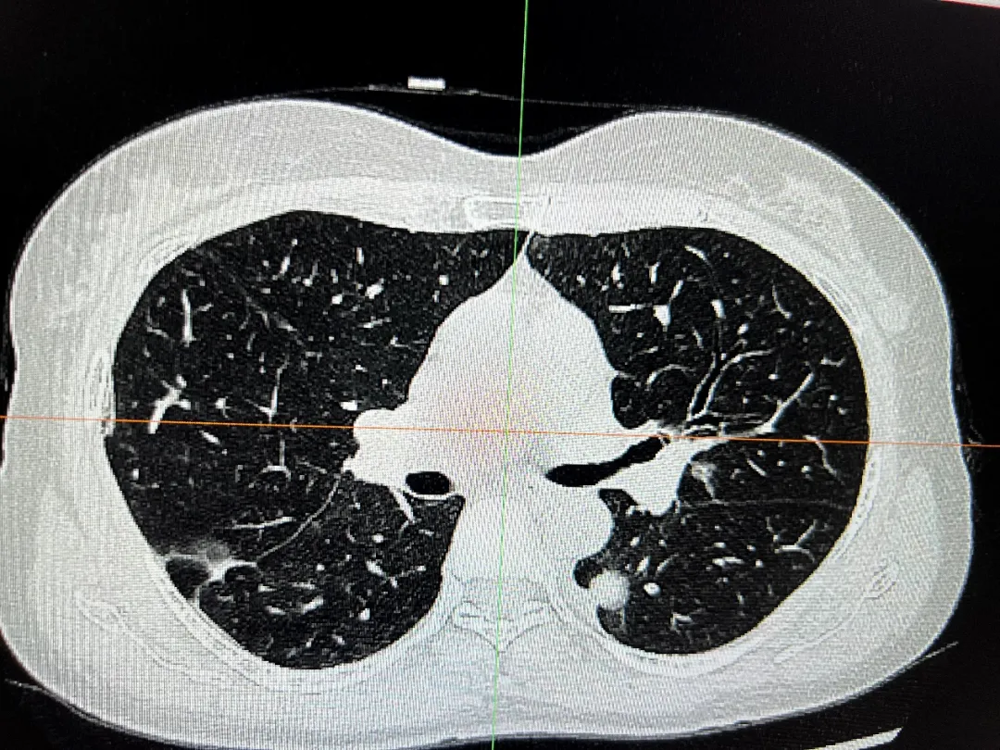

胸外科在复杂肺癌手术领域不断突破。一例55岁女性患者,CT发现双肺多发结节,高度怀疑多原发肺癌。面对传统分期手术创伤大、恢复慢的挑战,经多学科(MDT)充分评估、精密协作,胸外科团队勇于创新,成功为患者实施了“单孔胸腔镜下同期双侧肺癌根治术(右肺上叶切除+左肺下叶背段切除+双侧纵隔淋巴结清扫)”。手术一次完成,极大减少了患者痛苦与住院时间。术后病理证实为双侧原发性肺癌,分期分别为IIB期和IA2期。患者术后恢复迅速,第二天即可下床活动,并接受规范的靶向治疗(口服奥希替尼)。至今随访2年,无复发迹象,生活质量高。此案例彰显了我院胸外科在高难度、微创化、个体化肺癌手术治疗方面的卓越实力。

术前右侧胸部肿瘤

术前左侧胸部肿瘤